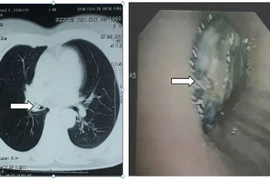

Ho suốt 3 năm mới phát hiện mắc hạt hồng xiêm trong phế quản

Bệnh nhân bị viêm phổi tái đi tái lại nhiều lần chỉ vì dị vật là hạt hồng xiêm nằm ở phế quản bên phải suốt 3 năm khiến